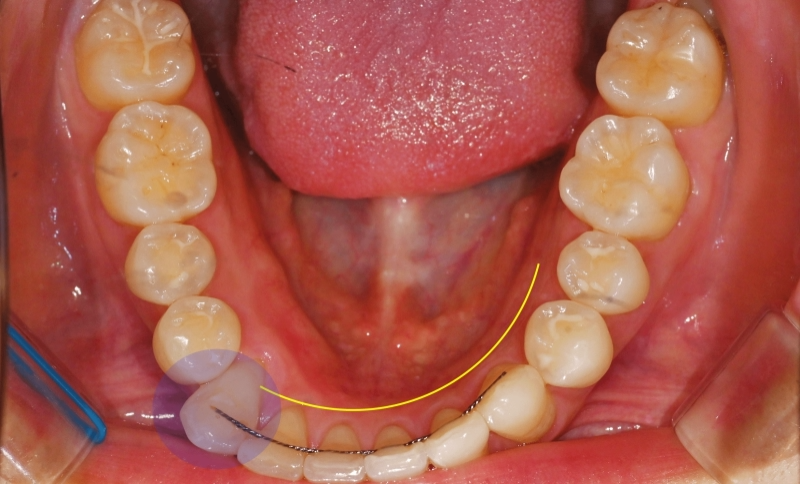

이어서 구강 내 사진을 보여드립니다.

우선 하악부터 살펴보면

가운데 중심을 기준으로 하여

오른쪽 송곳니 부분으로 중심이

쏠려있다는 양상을 보여줍니다.

이전에 붙여둔 유지 장치 retainer를

붙여둔 안쪽이 훤히 다 드러날 정도로

무언가 배열이 틀어졌음을 알 수 있습니다.

진료 중간 중간 촬영한 f.u 사진들 입니다.

진단 결과에 따라서 조금씩

치열이 개선 되는 것을

확인 할 수 있습니다.